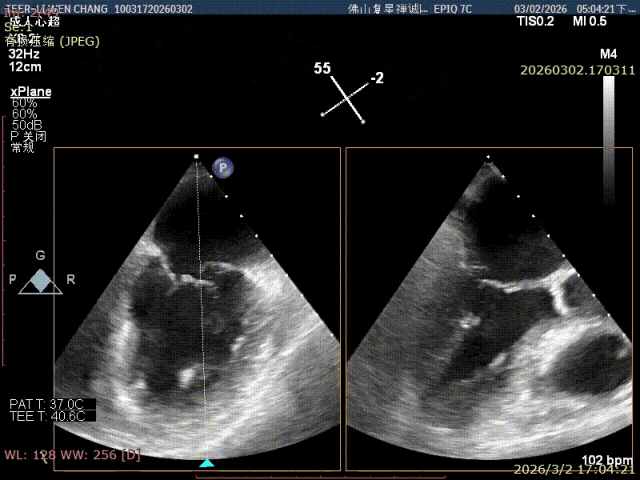

术前影像

X-plane 1区 后叶脱垂